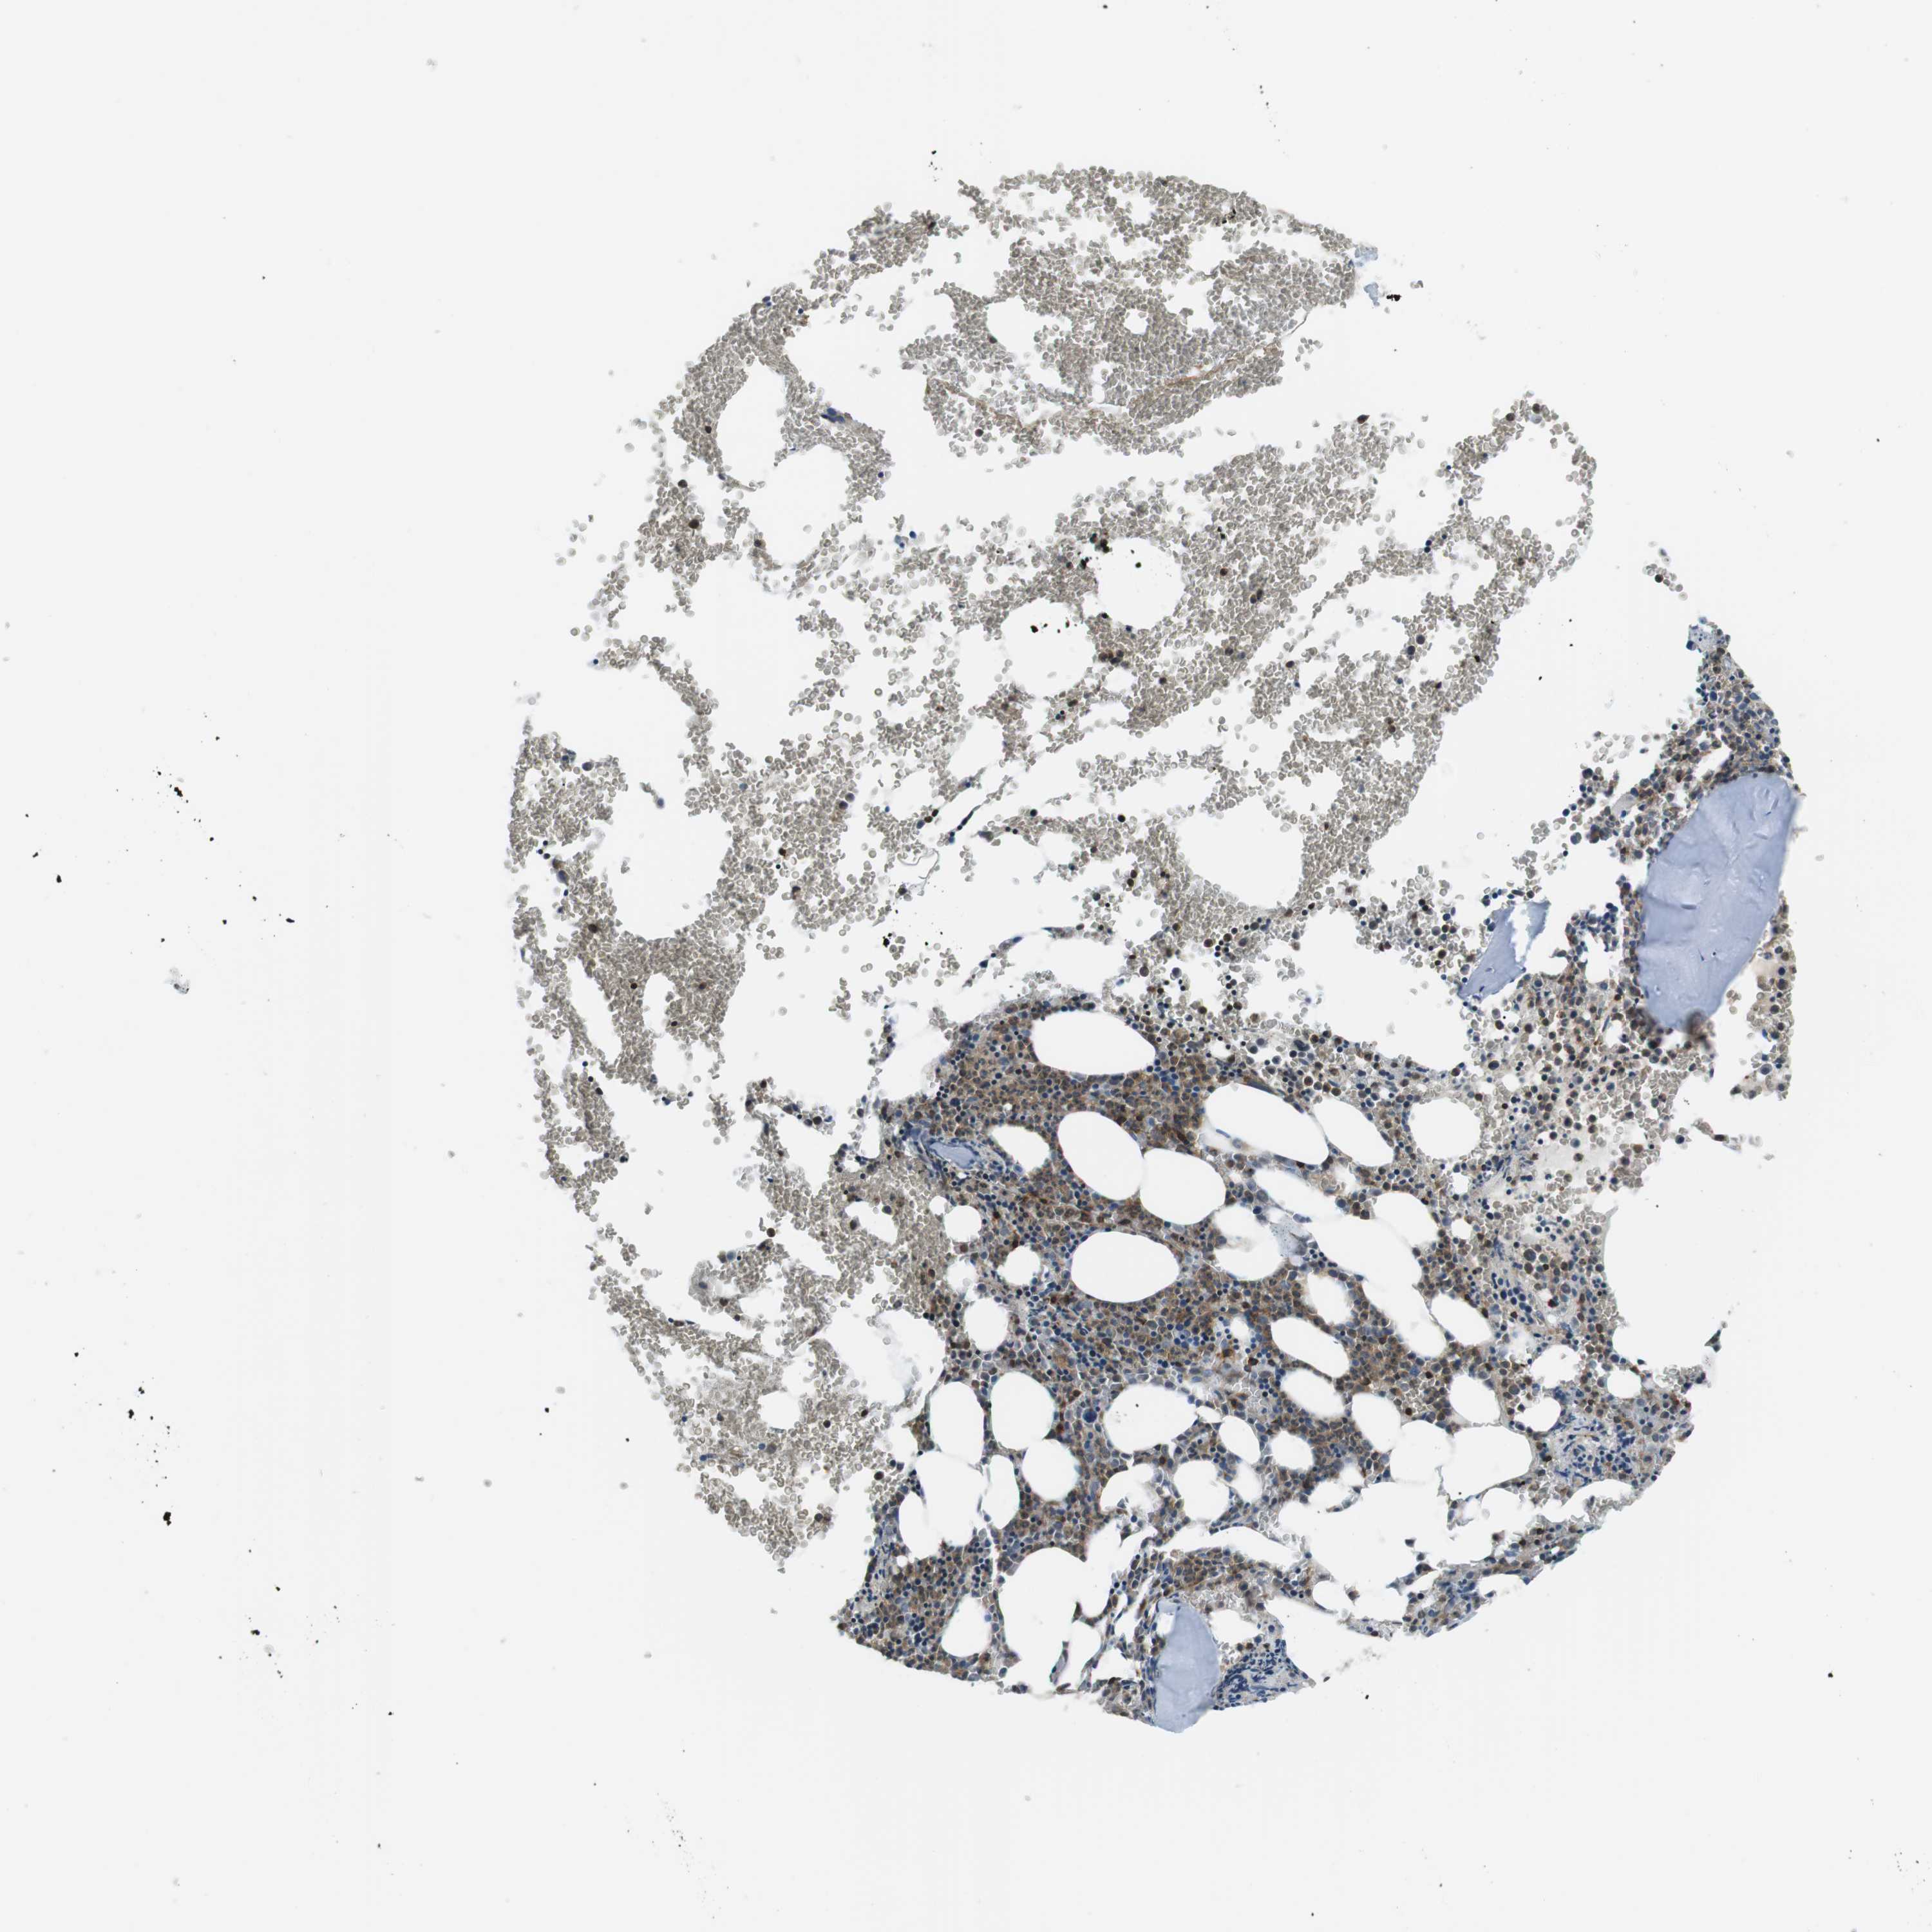

BONE MARROW - Antibody stainingi

Antibody staining in the annotated cell types in the current human tissue is reported as not detected, low, medium, or high, based on conventional immunohistochemistry profiling in selected tissues. This score is based on the combination of the staining intensity and fraction of stained cells. Each image is clickable and will lead to virtual microscopy that enables deeper exploration of all samples and also displays staining intensity scores, fraction scores and subcellular localization as well as patient and tissue information for each sample.

Antibody HPA015083Antibody CAB020840

Hematopoietic cells MediumMedium